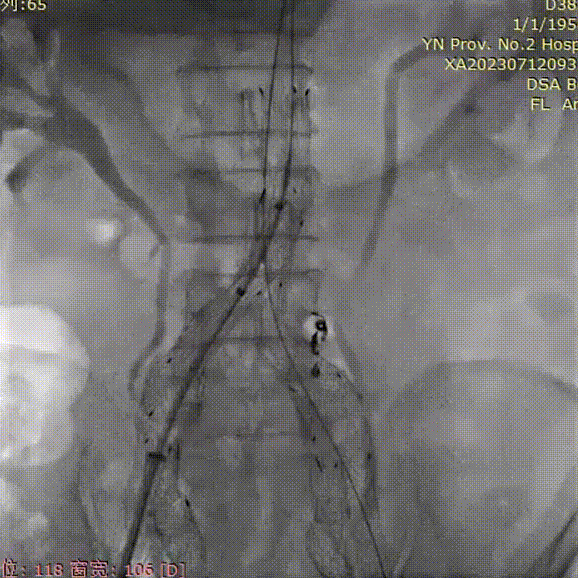

支架植入前造影

双侧股动脉入路,左侧置入18Fr 33cm GORE® DrySeal 亲水涂层导引鞘(以下简称“DSF导引鞘”),右侧置入12Fr 45cm DSF导引鞘;建立翻山通路后将标记猪尾导管头端置于肾动脉开口上方,做腹主动脉造影:显影显示双侧髂总动脉瘤;肾动脉开口到右髂内距离约200mm。